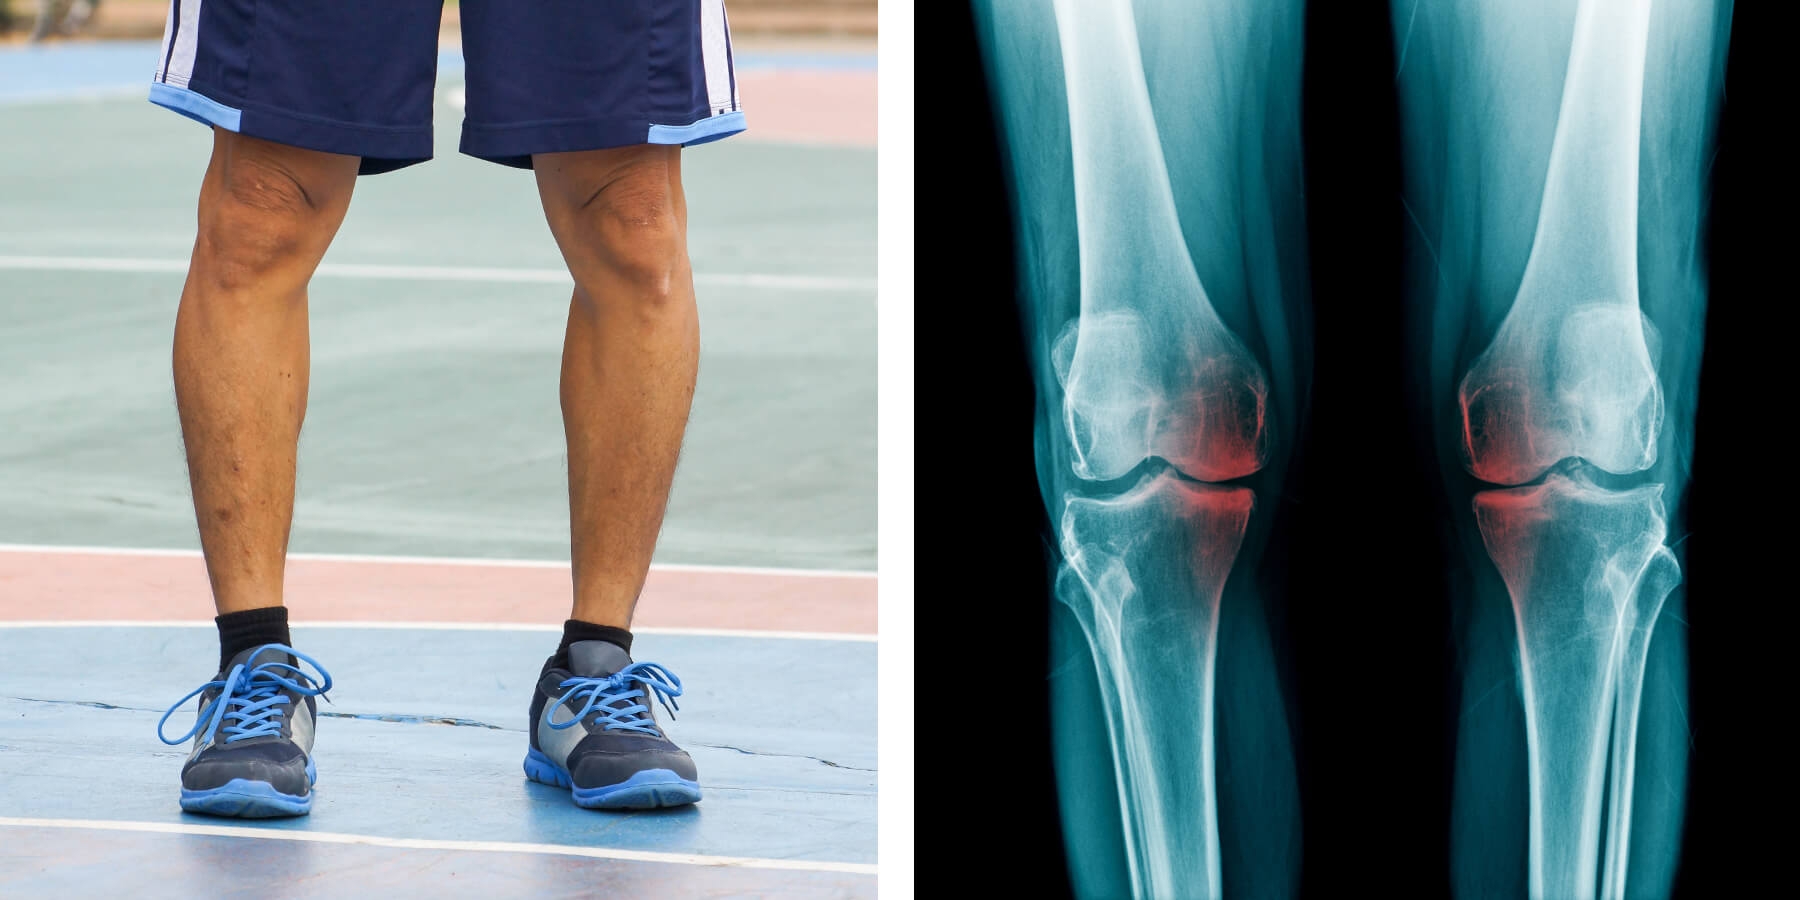

Bei O- oder X-Beinfehlstellungen verschleißt häufig nur ein Teil des Kniegelenkes. Wenn nur der innere (Varusgonarthrose) oder äußere (Valgusgonarthrose) Teil von Arthrose betroffen sind, kann eine Normalisierung der Beinachse zu Beschwerdefreiheit führen, ohne dass ein Gelenkersatz erfolgen muss.

Eine Beinachsaufnahme klärt, ob eine entsprechende Fehlstellung vorliegt. Diese ist nicht immer äußerlich zu erkennen!